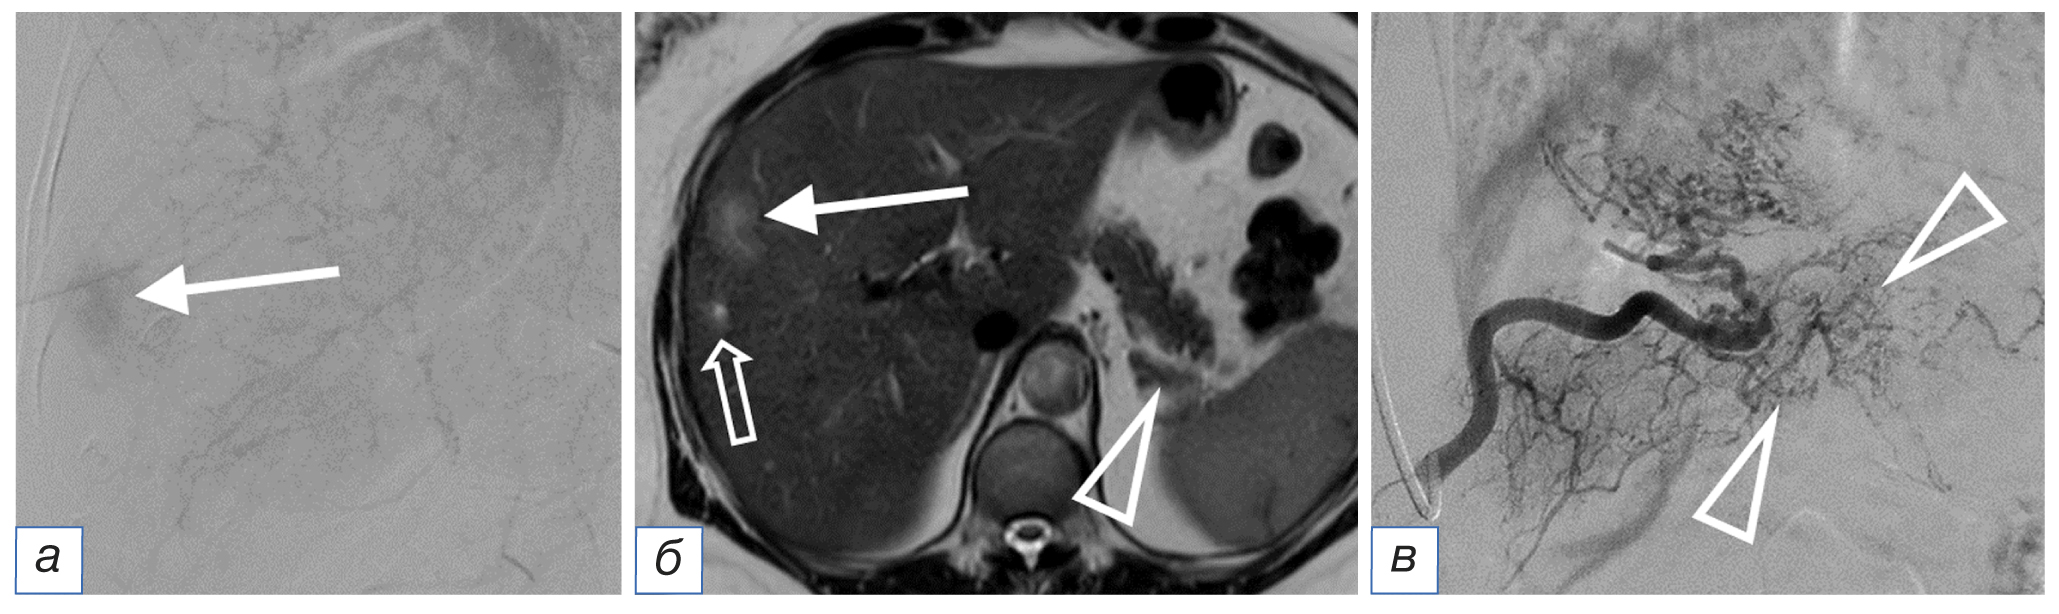

Ангиографическая картина во время операции также была разнообразна. В ряде случаев мы наблюдали достаточно интенсивное контрастирование паренхимы метастаза с разветвленной сетью афферентов (рис. 2), при этом наличие рядом расположенных очагов угадывалось только по перекалиброванным сосудам, отходящим в нетипичном месте (рис. 3). В ряде наблюдений вообще не было ангиографических признаков опухоли: в этом случае рентгенохирург мог ориентироваться только на данные диагностических методов. Заметим, что ангиоархитектоника основной опухоли не совпадала с ангиографической картиной метастазов в печени (рис. 3).

Рис. 3. Тот же пациент. Ангиографическая картина другого метастаза диаметром 3 см (а): несколько тонких перекалиброванных сосудов (стрелка), отходящих в нетипичном месте; магнитно-резонансная томография того же метастаза (б): щелевидный некроз в структуре (стрелка). / Fig. 3. The same patient. Angiographic picture of another metastasis with a diameter of 3 cm (а): several thin recalibrated vessels (arrow) exiting in an atypical place; magnetic resonance imaging of the same metastasis (б): slit necrosis in the structure (arrow).